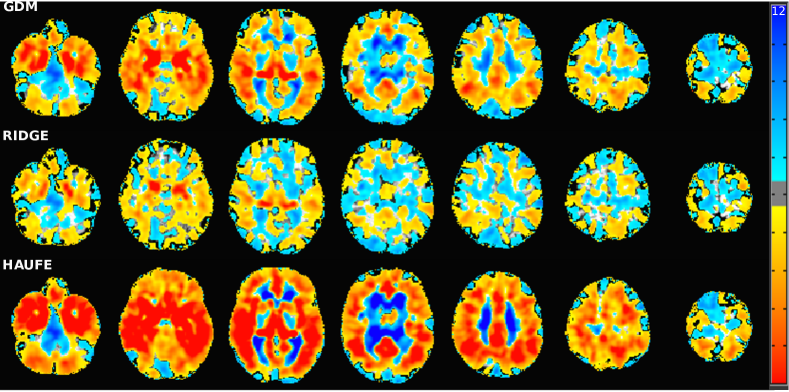

Statistical maps and p-values

To qualitatively assess and explain the predictive performance of the compared methods for the AD vs. CN scenario, we computed the model parameter maps using full resolution gray matter tissue density maps for the ADNI dataset (Fig. 4 top). Furthermore, since the null distribution of GDM, as well as ridge regression, can be estimated analytically, we computed p-values for the model parameters and displayed the regions surviving false discovery rate (FDR) correction [3] at level (Fig. 4 bottom).

The statistical maps demonstrated that both GDM and Haufe procedure yield patterns that accurately delineate the regions associated with AD, namely the widespread atrophy present in the temporal lobe, amygdala, and hippocampus. This is in contrast with the patterns found in ridge regression that resemble a hard to interpret speckle pattern with meaningful weights only on hippocampus. This once again confirmed the tendency of purely discriminative models to capture spurious patterns. Furthermore, the p-value maps of the Haufe method and ridge regression demonstrate the wide difference between features selected by generative and discriminative methods and how GDM strikes a balance between the two to achieve superior predictive performance.